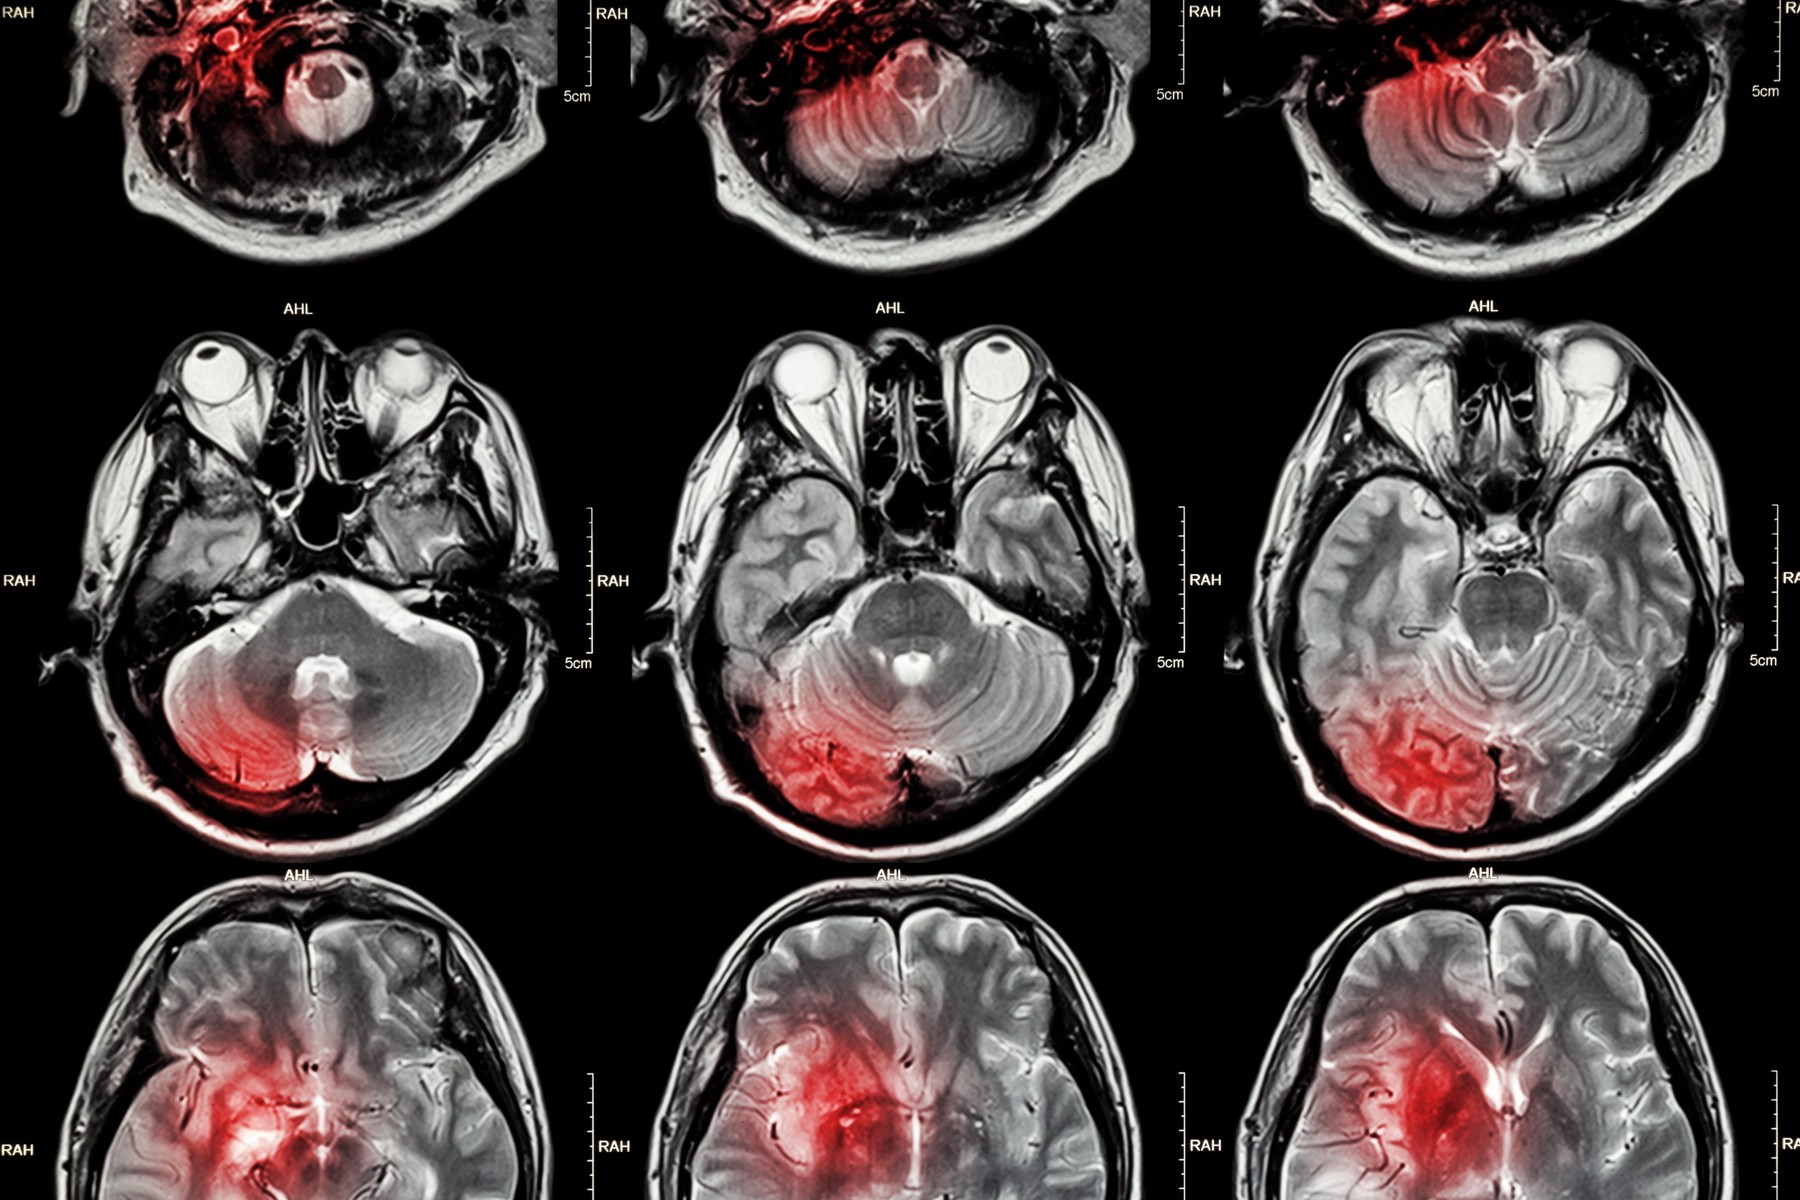

Postoje mnoge vrste tumora mozga, a mogu biti zloćudni ili dobroćudni. Kad je riječ o zloćudnim tumorima, neki od njih nastaju u mozgu pa se nazivaju primarnim tumorima na mozga. U drugim slučajevima, zloćudni tumor se širi iz drugog dijela tijela u mozak, što rezultira sekundarnim, metastatskim tumorima na mozgu.

Simptomi ovisno o lokaciji tumora

Neki simptomi mogu pružiti uvid u to gdje bi se tumor mogao nalaziti unutar mozga.